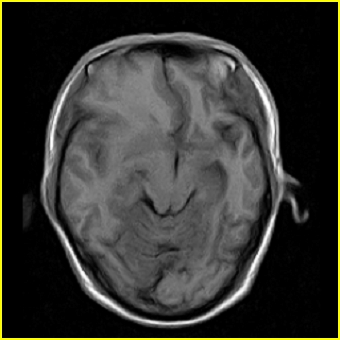

男,45岁,头部剧烈疼痛伴呕吐5天。

右侧额叶见较大的类圆形长t1信号环绕等t1环影,长t2信号环绕短等t2环,周围见明显水肿占位征,中线结构左移,男,45岁,头部剧烈疼痛伴呕吐5天。

右侧额叶,见一占位病灶,t1像病灶、水肿长t1;其间为短t1环行信号。t2像病灶、水肿长t2,其间为短t2环行信号。占位效应明显,中线左移,右测脑室受压闭塞。结合患者发病较急。首先考虑:右侧额叶脑脓肿形成。鉴别:1、转移瘤,多发多见2、胶质瘤。建议增强

1、脑脓肿可能大 2、右上颌窦炎 3、建议增强

个人认为转移瘤,右鼻窦占位性改变.